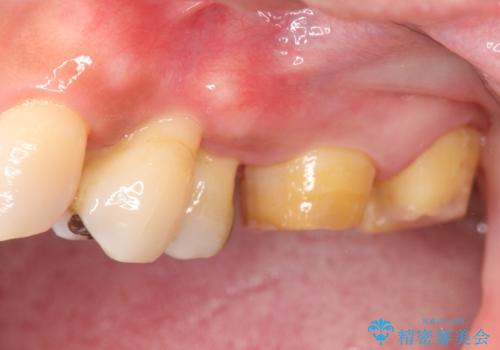

- 全体的に歯が揺れ、このままでは全て歯を失うのではないかと怖くなり歯周病治療を希望され来院されました。

歯列不正による第一小臼歯の骨吸収が認められ、機能咬合力の回復、大きな側方力に連結することで抵抗することのできるブリッジ補綴を選択しました。

歯周病による深いポケット・大きな側方力・短い臨床歯根・欠損の補綴、これらの問題を解決するために歯周補綴を兼ねたブリッジを選択しました。